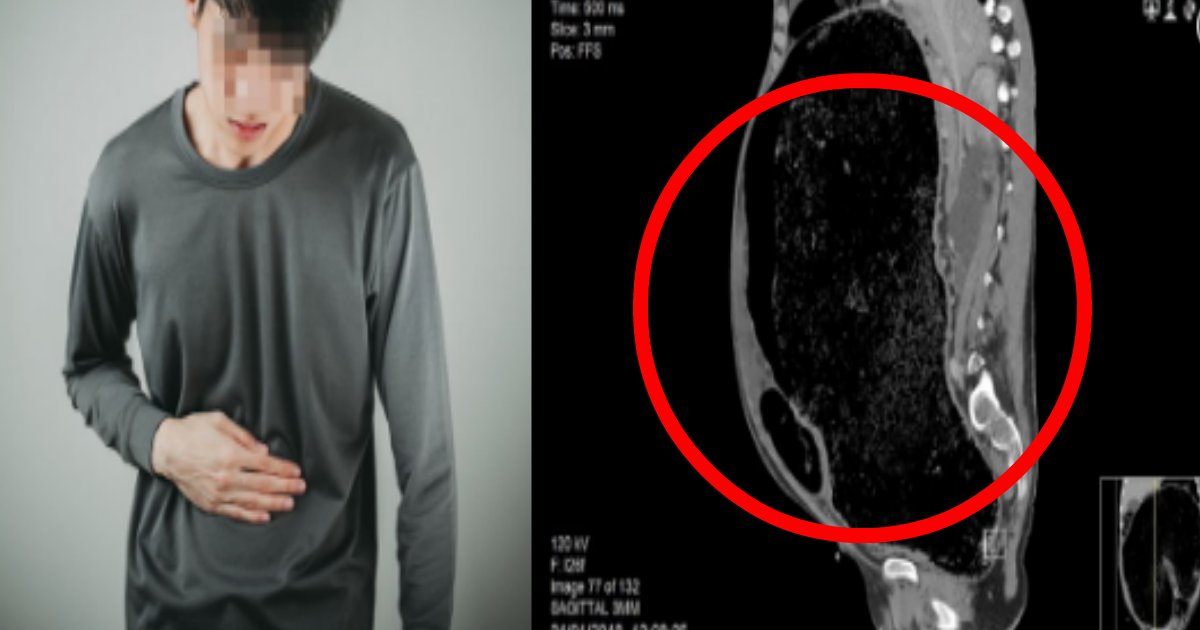

最近、アメリカのメディアが、お腹が大便に満たされ死にかけたある男性のレントゲン写真を公開しました。便秘を患ったこの男性はイギリスに住んでいる男性ということですが、彼は普段、慢性的な便秘があるものの、それは一時的な症状だと思い込み、放置してしまったようです。そのレントゲン写真というのが上の写真ですが、お腹が大便に満たされ、膨れ上がってしまっているのが分かります。

そこで、医者は精密検査のため、男性のお腹をレントゲンで撮影したのですが、その結果に医者もビックリ。先ほどのレントゲン写真の通り、大便がお腹の中に満たされたことで、周辺の臓器が機能しなくなっていたのです。そのせいで、男性の大腸は大きく損傷していました。特に大腸の下側の結腸は、大きく切れていたそうです。おまけに、腎臓もうまく機能しなくなったことで、心不全の症状もあらわれることに。